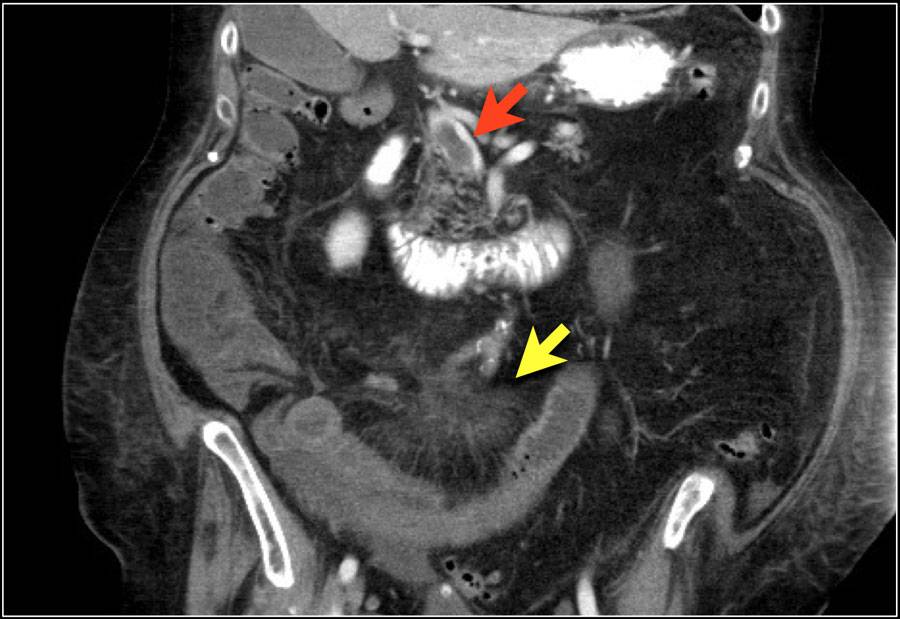

| Диагностика | Физикальный осмотр, анализы крови (лейкоцитоз, повышение лактата), рентгенография брюшной полости (признаки пневматоза кишечника, свободный газ), УЗИ, КТ-ангиография (золотой стандарт), лапароскопия. | Быстрая и точная диагностика критически важна для спасения жизни. |

Инструментальные методы исследования:

- Рентгенография органов брюшной полости – эффективна на ранних стадиях некроза.

- Радиоизотопное сканирование – позволяет выявить омертвевшие участки тканей и оценить степень поражения.

- Допплерография – используется при подозрении на проблемы с кровоснабжением кишечника.

- Ангиография – назначается для выявления тромбированных сосудов.

- Колоноскопия – проводится для оценки состояния стенок толстого кишечника.

Если невозможно точно определить область поражения и причину некроза, выполняется диагностическая лапароскопия. Этот метод позволяет визуально оценить состояние кишечных петель, степень поражения и выяснить причину некроза. При необходимости диагностическую лапароскопию можно преобразовать в лечебную процедуру.